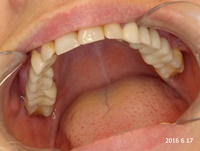

Przed trzema laty ząb 16 (prawa górna szóstka) był przeleczony endodontycznie i wykonano most. W ciągu 18 miesięcy od osadzenia mostu pacjentce kilka razy formował sie ropień dziąsła, osiem razy podawano antybiotyki. Gdy to nie pomagało, wykonano resekcję policzkowego korzenia zęba 16. Nie pomogło. W dalszym ciągu dochodziło do stanów zapalnych i antybiotykoterapii. W tym stanie pacjentka zgłosiła się, do naszego gabinetu. Zdjęto most, przeprowadzono ponowne leczenie kanałowe. Po sześciu miesiącach wykonano nowy most. Upłynęło półtora roku. Nie dochodzi do nawrotów stanu zapalnego, ani obrzęków. Ten przypadek pokazuje, dlaczego tak ważne jest poprawnie wykonane leczenie kanałowe, według nowoczesnego protokołu leczenia.